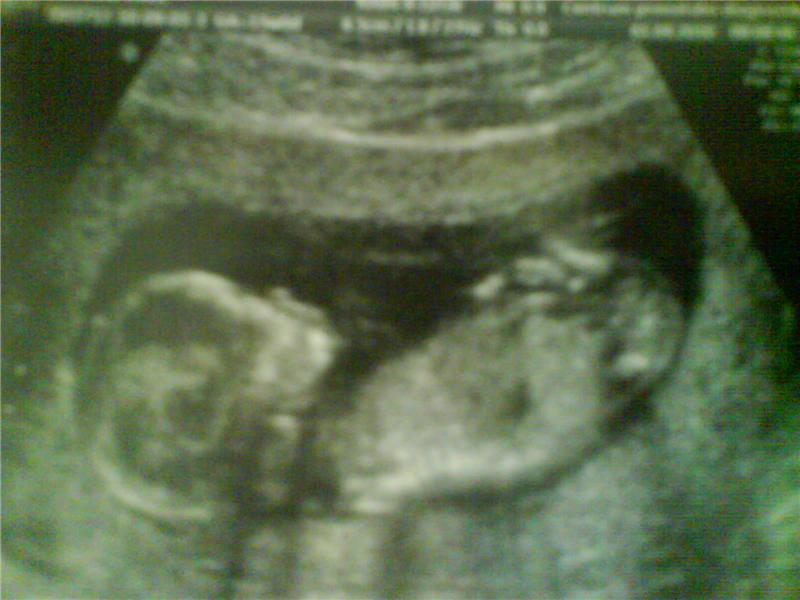

můj mimínek:-)